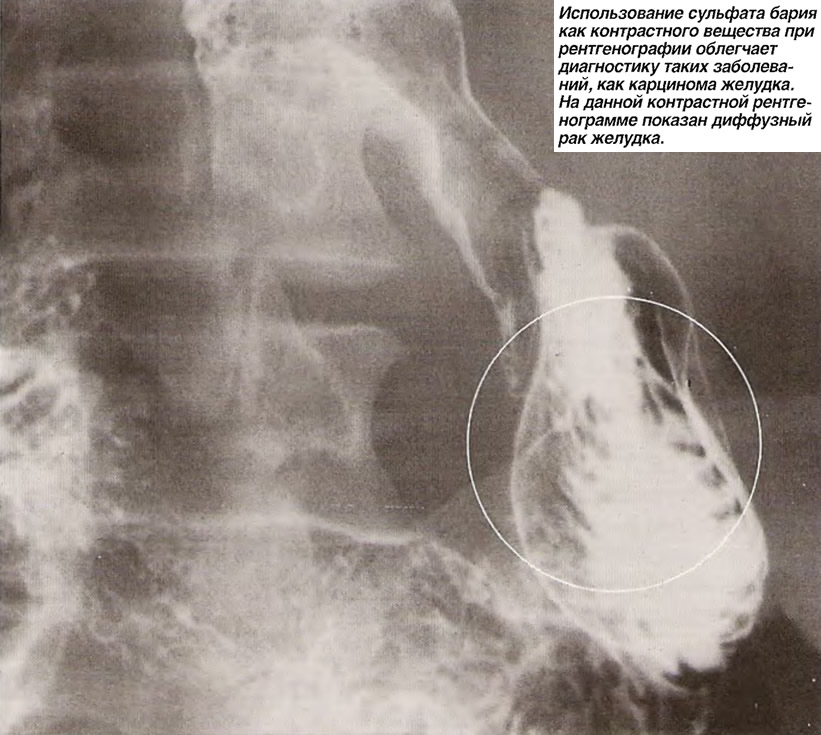

Рентгеноконтрастные Исследования Кишечника: Визуализация и Методики